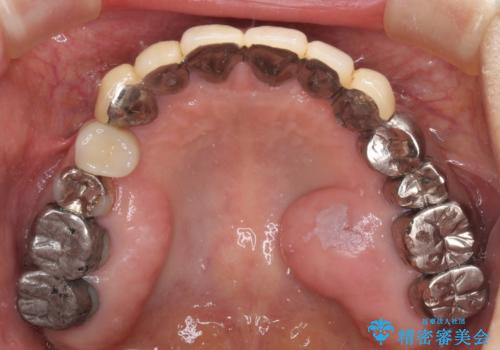

- 他院で抜歯が必要と診断され、インプラント治療を希望して来院された患者様です。

より審美的で、より機能的に優れた治療をご希望とのことであったので、ジルコニアカスタムアバットメントを用いたインプラント治療を行うこととしました。

ジルコニアカスタムアバットメントは、歯肉ラインに金属が見えにくいというだけでなく、クラウンを装着する土台の形が天然歯と近い形態となるため、清掃性が高く歯肉が腫れにくいというメリットがあります。

インプラントは、人工骨を用いた際の骨誘導能が比較的高いとさせるストローマン社のSLActiveを使用しました。